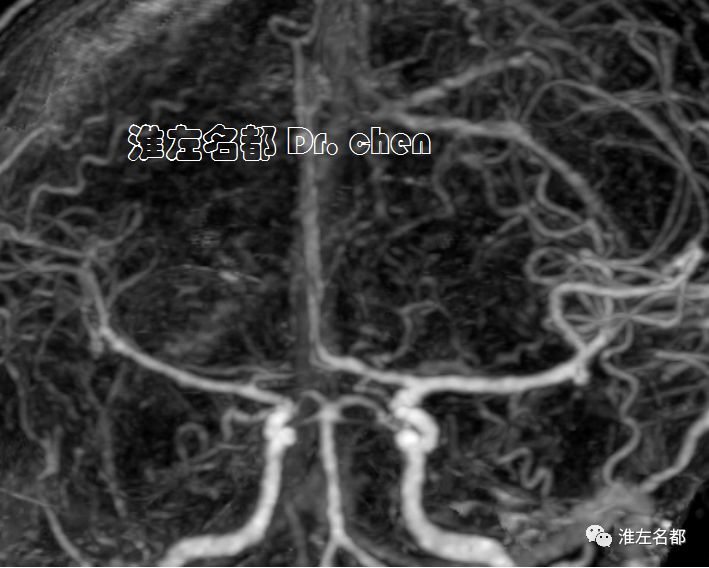

MRI

2019-9-19

△T2WI、T1WI、FLAIR和SWI:左侧半球大面积亚急性梗死伴渗血,局部软化坏死。

△3D-TOF-MRA:左侧大脑中动脉M1段和前动脉A1段管腔显影不规则;左侧大脑中动脉分支显影较对侧稀疏(考虑和大面积梗死后供血需求降低有关)。

△管壁高分辨MRI(增强T1-SPACE):左侧大脑中动脉主干管壁未见异常(橙箭),左侧颈内动脉远端管壁增厚和强化(红箭)。

△管壁高分辨MRI(增强T1-SPACE):左侧颈内动脉末端检测到夹层“内膜征”(橙箭)。